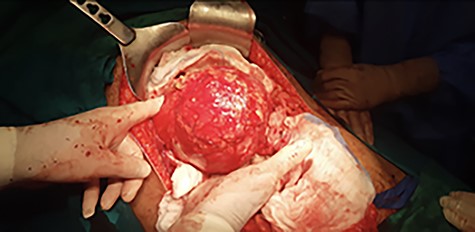

Surgery was performed via double Kocher incision (subcostal). Intraoperative examination revealed a cystic mass covered by great omentum and adhesions (Fig. 2). The operative field was packed with hypertonic saline gauze and compresses to isolate the lesion and prevent disease dissemination to other parts of the abdomen. Subsequently, liver mobilization was performed. Meticulous dissection was performed using the ultrasonic device Thunderbeat (Olympus America, USA) as the energy source. The cystic lesion (approximate diameter: 20 cm) originated from the segment IVb of the liver and was firmly adhered to the gall bladder. There was mild fibrosis of the gall bladder, however, it did not contain any gallstones. Both the cystic duct and the common bile duct were normal in diameter. Cholecystectomy was necessary for better access and mobilization of the cystic mass; the cystic mass was resected intact and completely along with the involved part of segment IVb liver (total closed cysto-pericystectomy). The removed intact specimen is shown in Figure 3. In addition, there was another small cyst (approximate diameter: 5 cm) in close proximity to the main cyst; it was removed completely by opening the cyst (endocystectomy). Intraoperative blood loss was minimal (<100 mL). Two closed drains were left in place prior to closure of the abdomen. Postoperatively, prophylactic antibiotics and albendazole were administered. The postoperative period was uneventful and the patient was discharged on the eighth postoperative day in good condition.

Intraoperative view showing the cystic mass covered by great omentum and adhesions.